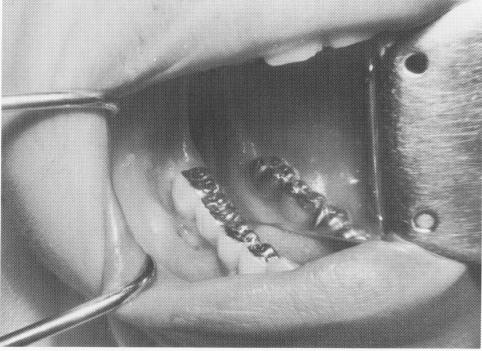

The restoration was tried in the mouth before the implant was inserted, and all necessary adjustments were accomplished (Fig. 8-79). The restoration was then removed, and the vent-plant with a Dacron sleeve was screwed into the bone (Fig. 8-80). (It was hoped that the porous character and slightly irritating quality of the Dacron would pro-mote closer adaptation of the collagenous tissue around the post. Approximately three dozen cases using Dacron sleeves screwed into bone have been done, and all are still in the mouths functioning well. The results are still unsubstantiated by tissue biopsies.) The restoration was then cemented into position with hard cement (Fig. 8-81) and radiographed (Fig. 8-82).

Fig. 8-81. The prosthesis is cemented over the implant post and into the Class II inlay preparations.